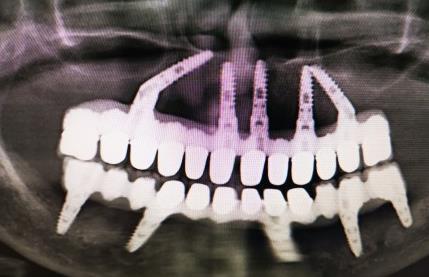

醫生強調,其實不必要做全口種植牙,可以在口腔內(nei) 植入幾顆種植牙後,在上麵做烤瓷橋或者是做覆蓋義(yi) 齒的形式,一般植入4~8顆種植牙,這樣可以節省很多的種植牙費用,而且也可以獲得很好的牙齒咀嚼結果以及穩定和美觀。